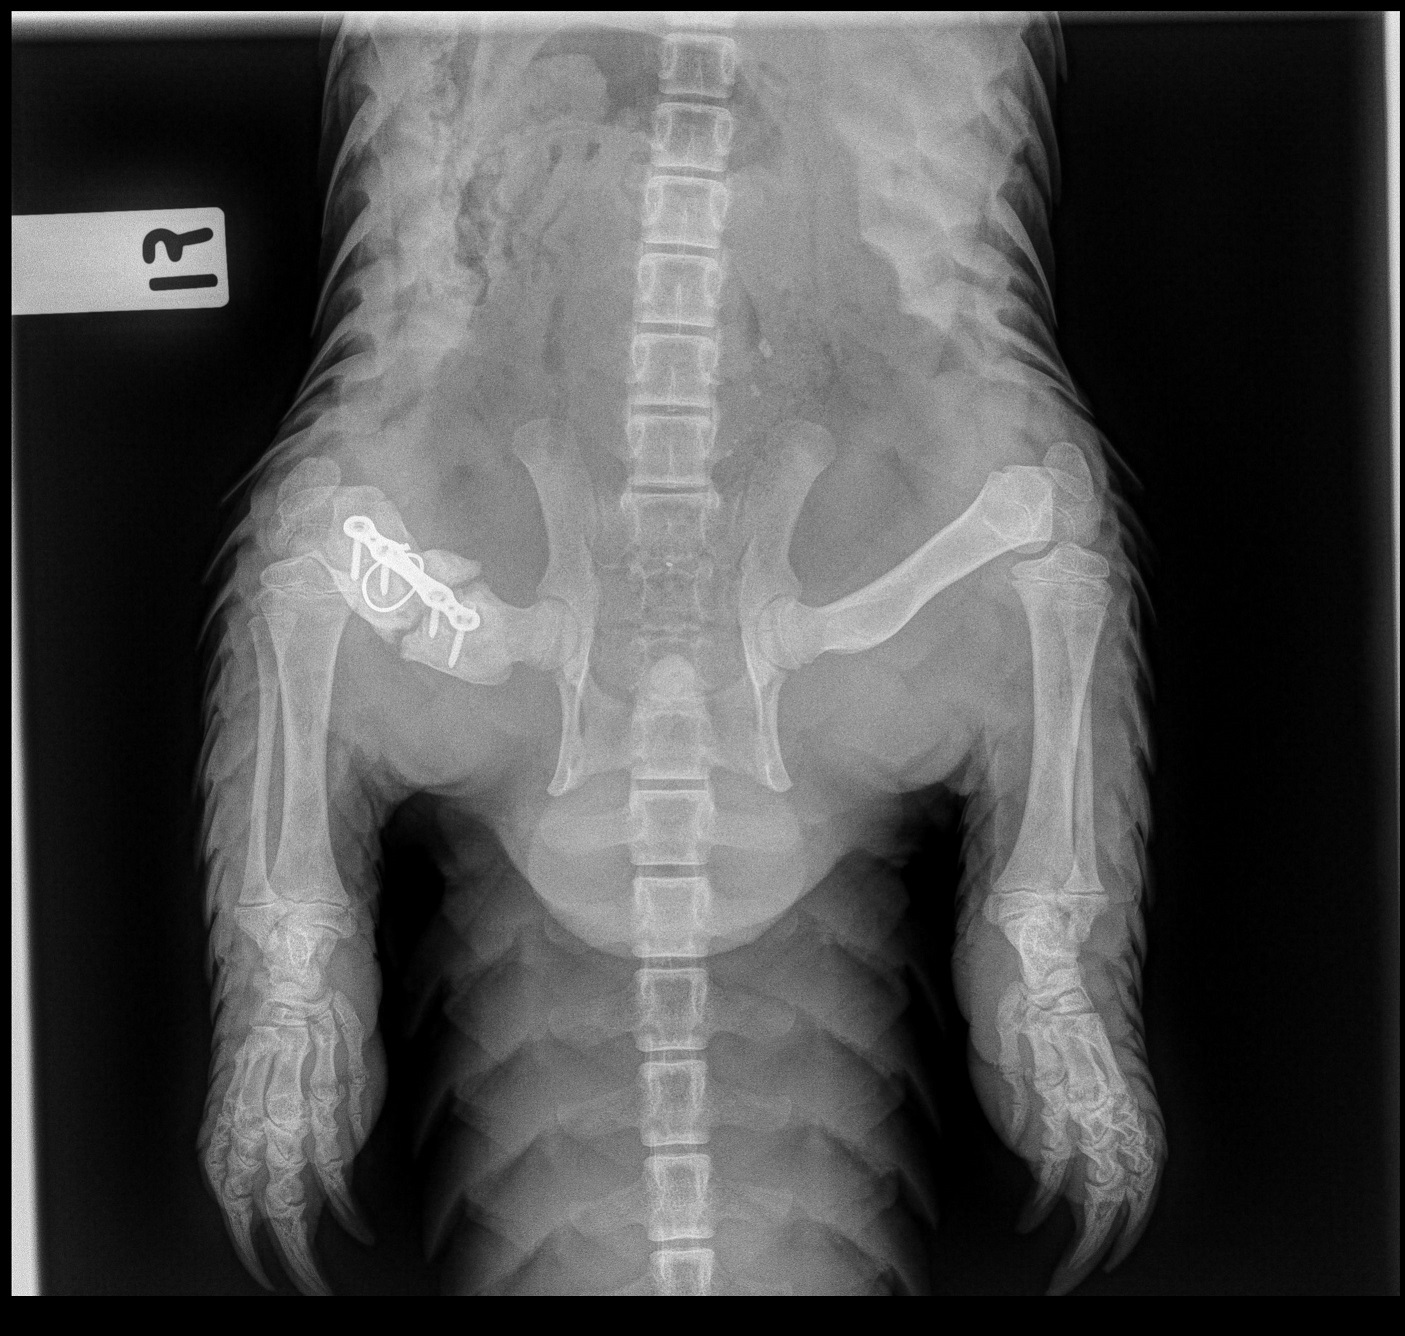

Critically endangered Sunda pangolin Berani was rescued and sent to Wildlife Reserves Singapore’s Wildlife Heathcare and Research Centre in July 2018, where he was found to have a fractured right femur.

Close-up of Berani’s X-ray taken on 28 Jan 2019 showing that the implants are in place and that bone healing has been recorded.